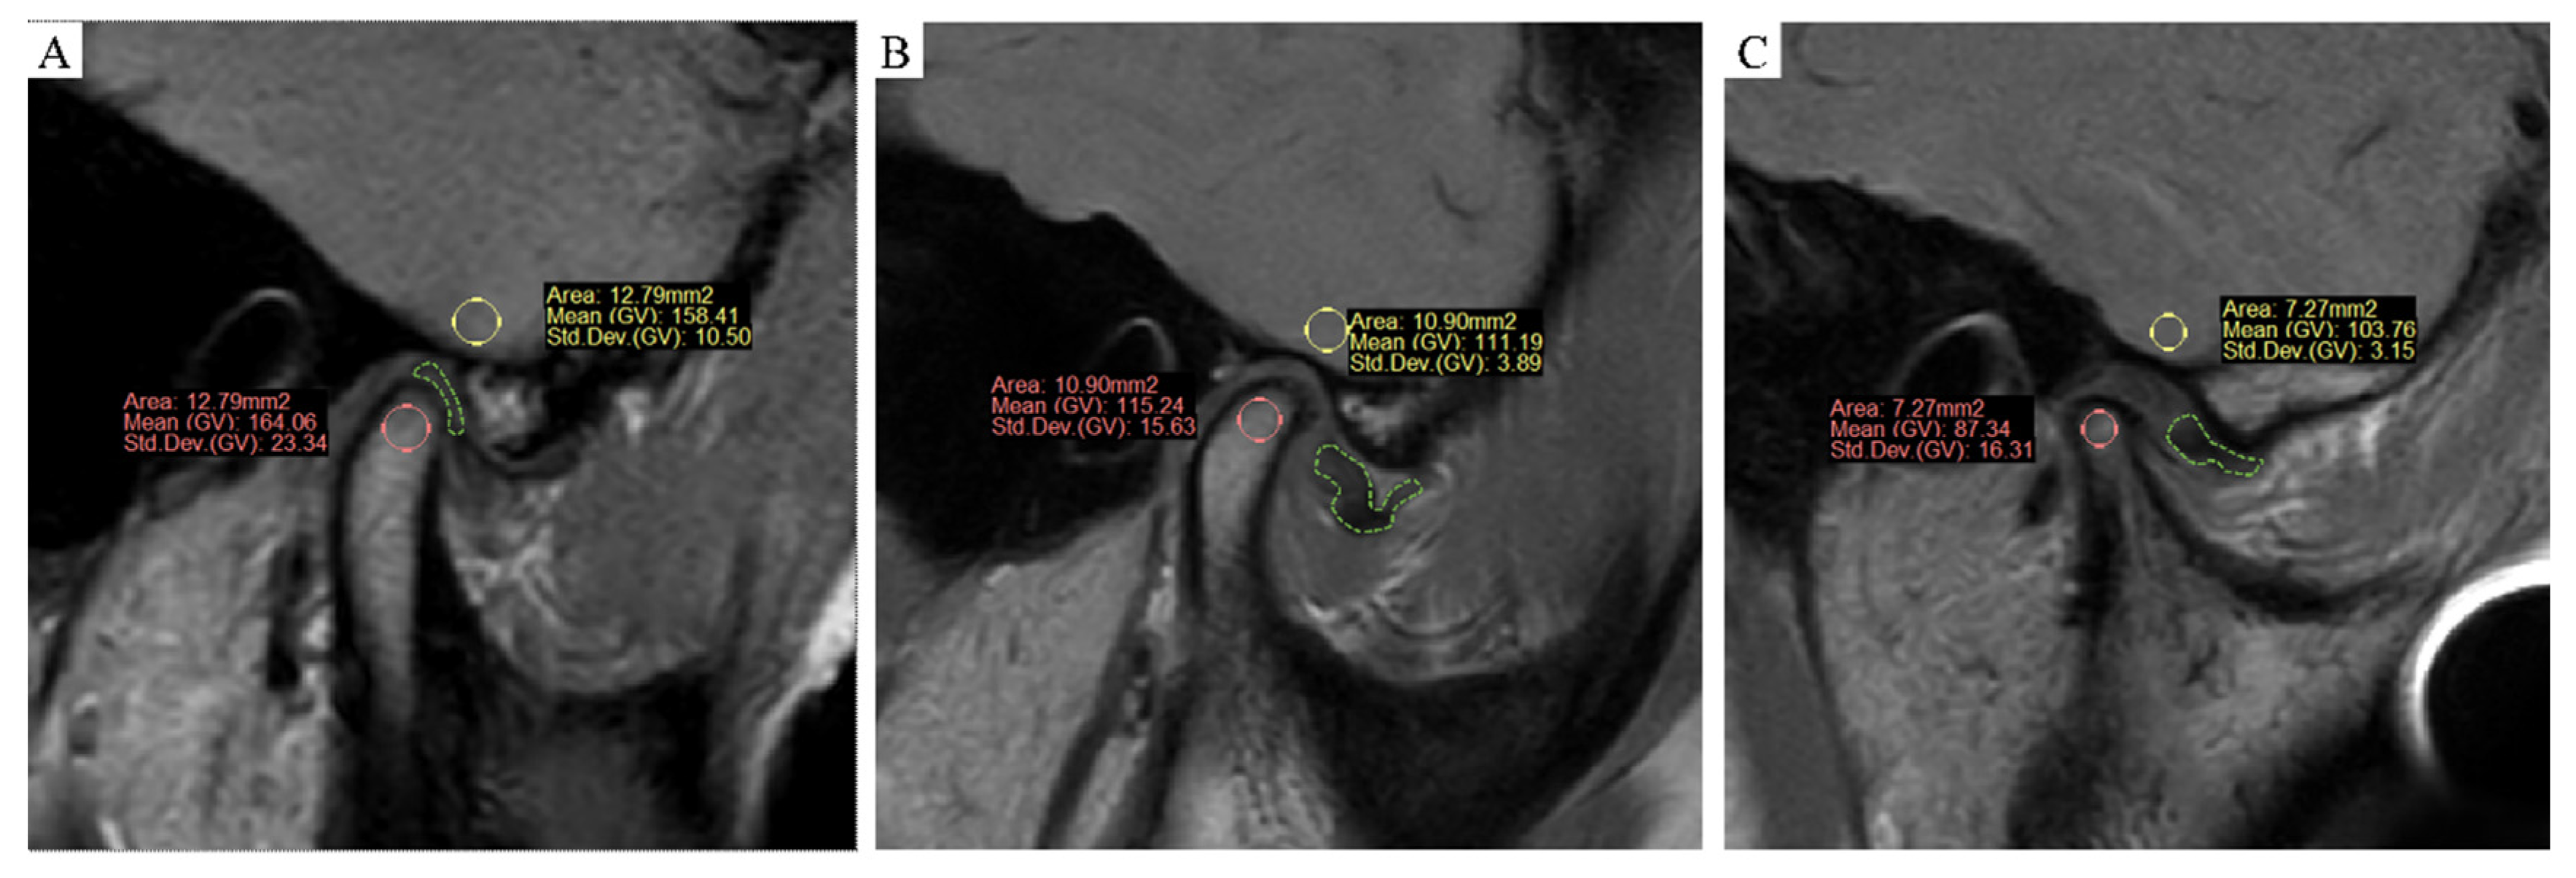

The MRI images were processed by ProPlan CMF software (version 1.4, Materialise, Leuven, Belgium). Three MRI images were obtained at the middle third of the condyle at each side, where the cross-section was largest. The MRI of the condyle was performed at the condylar head and the inner condylar cortex, and the largest inscribed circle in each slice was used for sampling. Measurement was repeated three times for each side. For the cerebral cortex, MRI was performed at the cerebral cortex at the inferior temporal gyrus located at the same position of the condyle. Three measurements were taken for the inscribed circle of the same area for each side, and the average was reported. The MSI of the condyle (MSI1) and cerebral cortex (MSI2) were obtained, and then the SIR (MSI1/MSI2) between them was calculated. Samples were presented as follows (Figure 1A–C). A total of 120 condyles were measured independently by a surgeon and a radiologist.

(A–C) MRI sampling and measurement, oblique sagittal at closed mouth PDWI. (A) Normal group (group 1): the articular disc marked in green was in a normal position, and the status of the condyle was healthy. (B) ADD without the CR group (group 2): ADD occurred, but the status of the condyle was still healthy. (C) ADD with CR group (group 3): not only ADD occurred, but the shape and volume of the condyle was significantly resorbed.